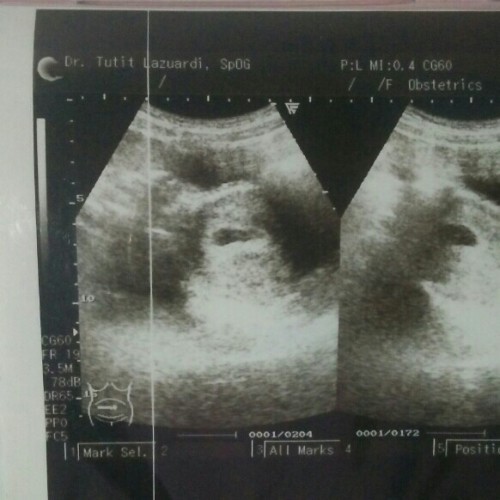

Usg

disini ada gk yg prtma kali usg trus janin blm keliatan? aku usg d usia 6mnggu6hari tapi baru kantungnya sj yg ada tapi janin blm.. sedih pas liatnya, tapi dokter kasih vitamin trus disuruh balik 2 mnggu lagi.. kira2 janinnya msh trllu kecil makany blm keliatan atau BO?